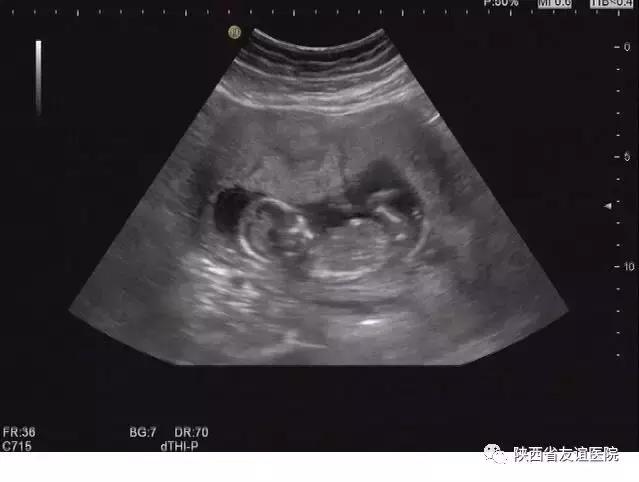

早中孕B超图

或许是基于我们前面说到的怕B超对胎儿造成伤害,亦或是因为已经生产过一个健康宝宝的缘故,很多孕妇认为早期不需要做B超检查,到3个月以后建档时再好好查就可以了。

其实,这些想法都是不对的。孕早期是排除宫外孕和胚胎是否正常发育的关键时期,早期的检查可以明显地降低事故的发生率。在平时的检查中,经常会看到这样一些孕妇,来产检时是以孕12周伴阴道出血来就诊的,但是B超显示的发育程度与孕周明显不符,甚至出现了胚胎停育的现象;还有一些人甚至有严重的腹痛及阴道出血,并伴有休克,甚至危及生命,经B超检查诊断为宫外孕破裂,。而这些人中,很多是第一次进行B超检查的。

那么,如果在孕早期6周左右就能按时进行B超检查,这样的事故或者遗憾是不是将会大大减少呢?答案是肯定的。因此,我们还是建议孕早期6周左右需要进行一次有效的B超检查。